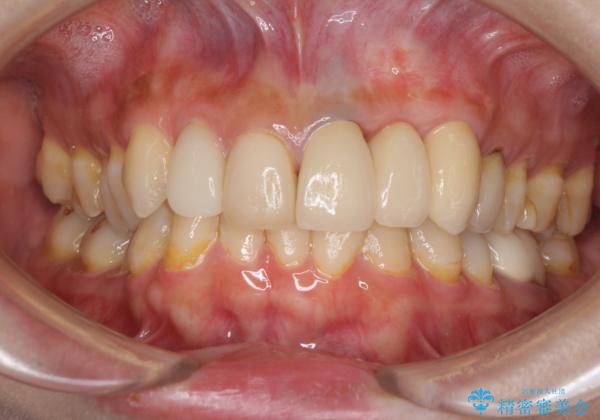

歯肉移植を用いた前歯のオールセラミックブリッジ

インプラントかブリッジか悩むところでしたが、既に治療されている前歯のクラウン周りの変色が気になっていたため、ブリッジにより色調を合わせたオールセラミックを装着することを選択しました。

歯肉ラインや歯の形態、色調を整えることができ、患者様には大変満足していただきました。